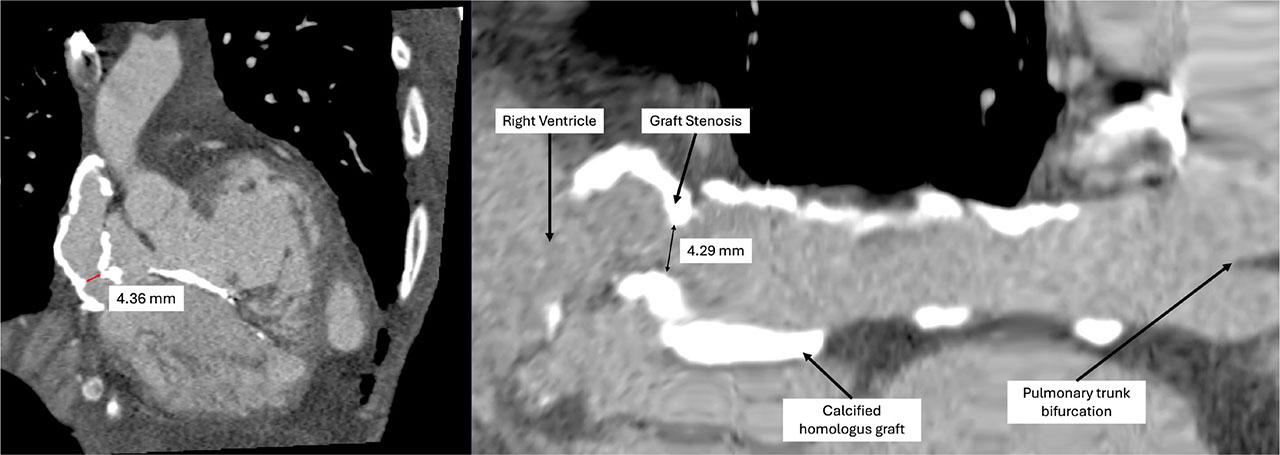

A transthoracic echocardiography was performed in the emergency department and showed severe tricuspid regurgitation, severe pulmonary hypertension, and a decrease in left ventricular ejection fraction (LVEF) to 45% without any evidence of endocarditis (the last echocardiography, performed three months prior to admission, showed mild tricuspid regurgitation and a LVEF of 60%). A transesophageal echocardiography was attempted, but the patient was uncooperative and refused the procedure. Following these findings, we decided to admit the patient to the Internal Medicine Clinic for further investigation and specialised treatment. The patient’s condition remained stable, with a qSOFA score of 1 point, heart rate of 115/min, blood pressure of 110/70 mmHg without positive inotropes, oxygen saturation of 90% with a non-rebreather mask, and after intravenous hydration, serum creatinine decreased to 1.62 mg/dL (creatinine clearance 41 ml/min). Congestive heart failure treatment was initiated, including Ramipril 2.5 mg once a day (Helcor Pharma, Romania), Carvedilol 6.25 mg twice daily (Labormed, Romania), Spironolactone 25 mg once a day (Terapia, Romania), Dapagliflozin 10 mg once a day (AstraZeneca Pharma, Sweden) and Furosemide 100 mg a day by continuous intravenous infusion (Hameln Pharma GMBH, Germany). In addition, thromboprophylaxis with low-molecular-weight heparin, Enoxaparin 40mg (Sanofi, France), a proton pump inhibitor, Pantoprazole 40 mg (Rompharm Company, Romania) and an antipyretic, Paracetamol 1000mg (Braun, Germany) were administered. Two days after admission, the urine culture was positive for Candida lusitaniae and antifungal treatment with Fluconazole 200mg twice daily (Arena Group S.A, Romania) was initiated, while blood cultures and nasopharyngeal swabs remained negative. Given the improvement in renal function, we decided to perform a cardiac CT scan with intravenous contrast, which revealed a stenosis of the homograft connecting the right ventricle to the pulmonary artery (Figure 2, 3).

Cardiac CT scan with intravenous contrast: Homograft stenosis-reduction in the diameter of the conduit connecting the right ventricle to the pulmonary artery from 14 mm to 4.29 mm

When faced with a hyperpirexic patient with signs and symptoms of heart failure, the first imaging strategy was transthoracic echocardiography performed in the emergency department, revealing the first changes that could relate to the patient’s symptoms, namely newly developed, severe tricuspid regurgitation and a decrease in left ventricular ejection fraction to 45%. However, given the patient’s history of the Rastelli procedure, we considered the possibility that the severe tricuspid regurgitation discovered on echocardiography was secondary to pressure and volume overload of the right ventricle caused by conduit stenosis, this being the most common complication and cause of reintervention, as stated before [11]. To assess the integrity of the homograft, we performed a cardiac computed tomography study augmented by intravenous contrast, which confirmed the suspicion of graft stenosis. Although the cardiac CT study aided in diagnosing this complication, it is important to note that magnetic resonance imaging would have allowed a better quantification of the integrity of the homograft, especially in adults after surgery [12, 13], but this could not be performed due to technical unavailability. In order to determine the cause of hyperpirexia, in addition to bacteriological cultures, we considered performing a contrast-enhanced computed tomography study of the abdomen and pelvis, which ruled out any additional or alternative source of infection, while revealing splenic infarctions. This imaging find led to raising the suspicion of infectious endocarditis.

As for the cause of death, considering the patient’s past struggle with chronic respiratory failure (exhibiting oxygen saturation levels of around 80–85% in ambient air), the abrupt clinical and paraclinical decline triggered by the onset of severe dispnoea, tachypnea and hypercapnic respiratory acidosis led to a further exacerbation of chronic respiratory failure. Thus, considering the acute on chronic respiratory failure, we concluded that stenosis of the conduit was the main cause of death. The conduit stenosis mechanism was due to a combination of compression caused by pectus excavatum and further degenerative processes, as evidenced by extensive calcifications on cardiac CT. Given the chronic nature of the conduit’s degenerative process and the sudden worsening of the clinical picture, we establised that the infectious endocarditis on a foreign body to be the mechanism for the worsening of stenosis. Additionally, we interpreted the newly developed tricuspid regurgitation as an adaptive response to volume overload and increased right ventricular pressure. Given the splenic infarctions present in our patient, we can reasonably accept the presence of an embolic source, in the context of endocarditis, releasing septic emboli into the bloodstream that reach cerebral and pulmonary circulations. Due to the rapid progression of events and the patient’s critical condition, a cranial CT scan could not be performed to confirm or rule out an ischemic stroke. Furthermore, we hold no evidence to sustain the release of septic emboli into the pulmonary circulation, which could have led to acute respiratory failure. A relevant case in literature is that of a 19-year-old male, diagnosed with infectious endocarditis with Candida spp, complicated by pulmonary infarction and pulmonary mycotic abscesses, who died of massive pulmonary hemorrhage, diagnosed postmortem, 6 months after undergoing a second Rastelli operation for conduit stenosis [19]. Another factor considered was septic shock in the context where antibiotic treatment was not adequate without clear pathogen isolation. However, due to the decrease in inflammatory markers, we are able to sustain that sepsis was not the decisive factor that caused death. Definitive autopsy findings are unavailable to us, as the patients’ family refused the procedure (as permited by current law procedures in our country).